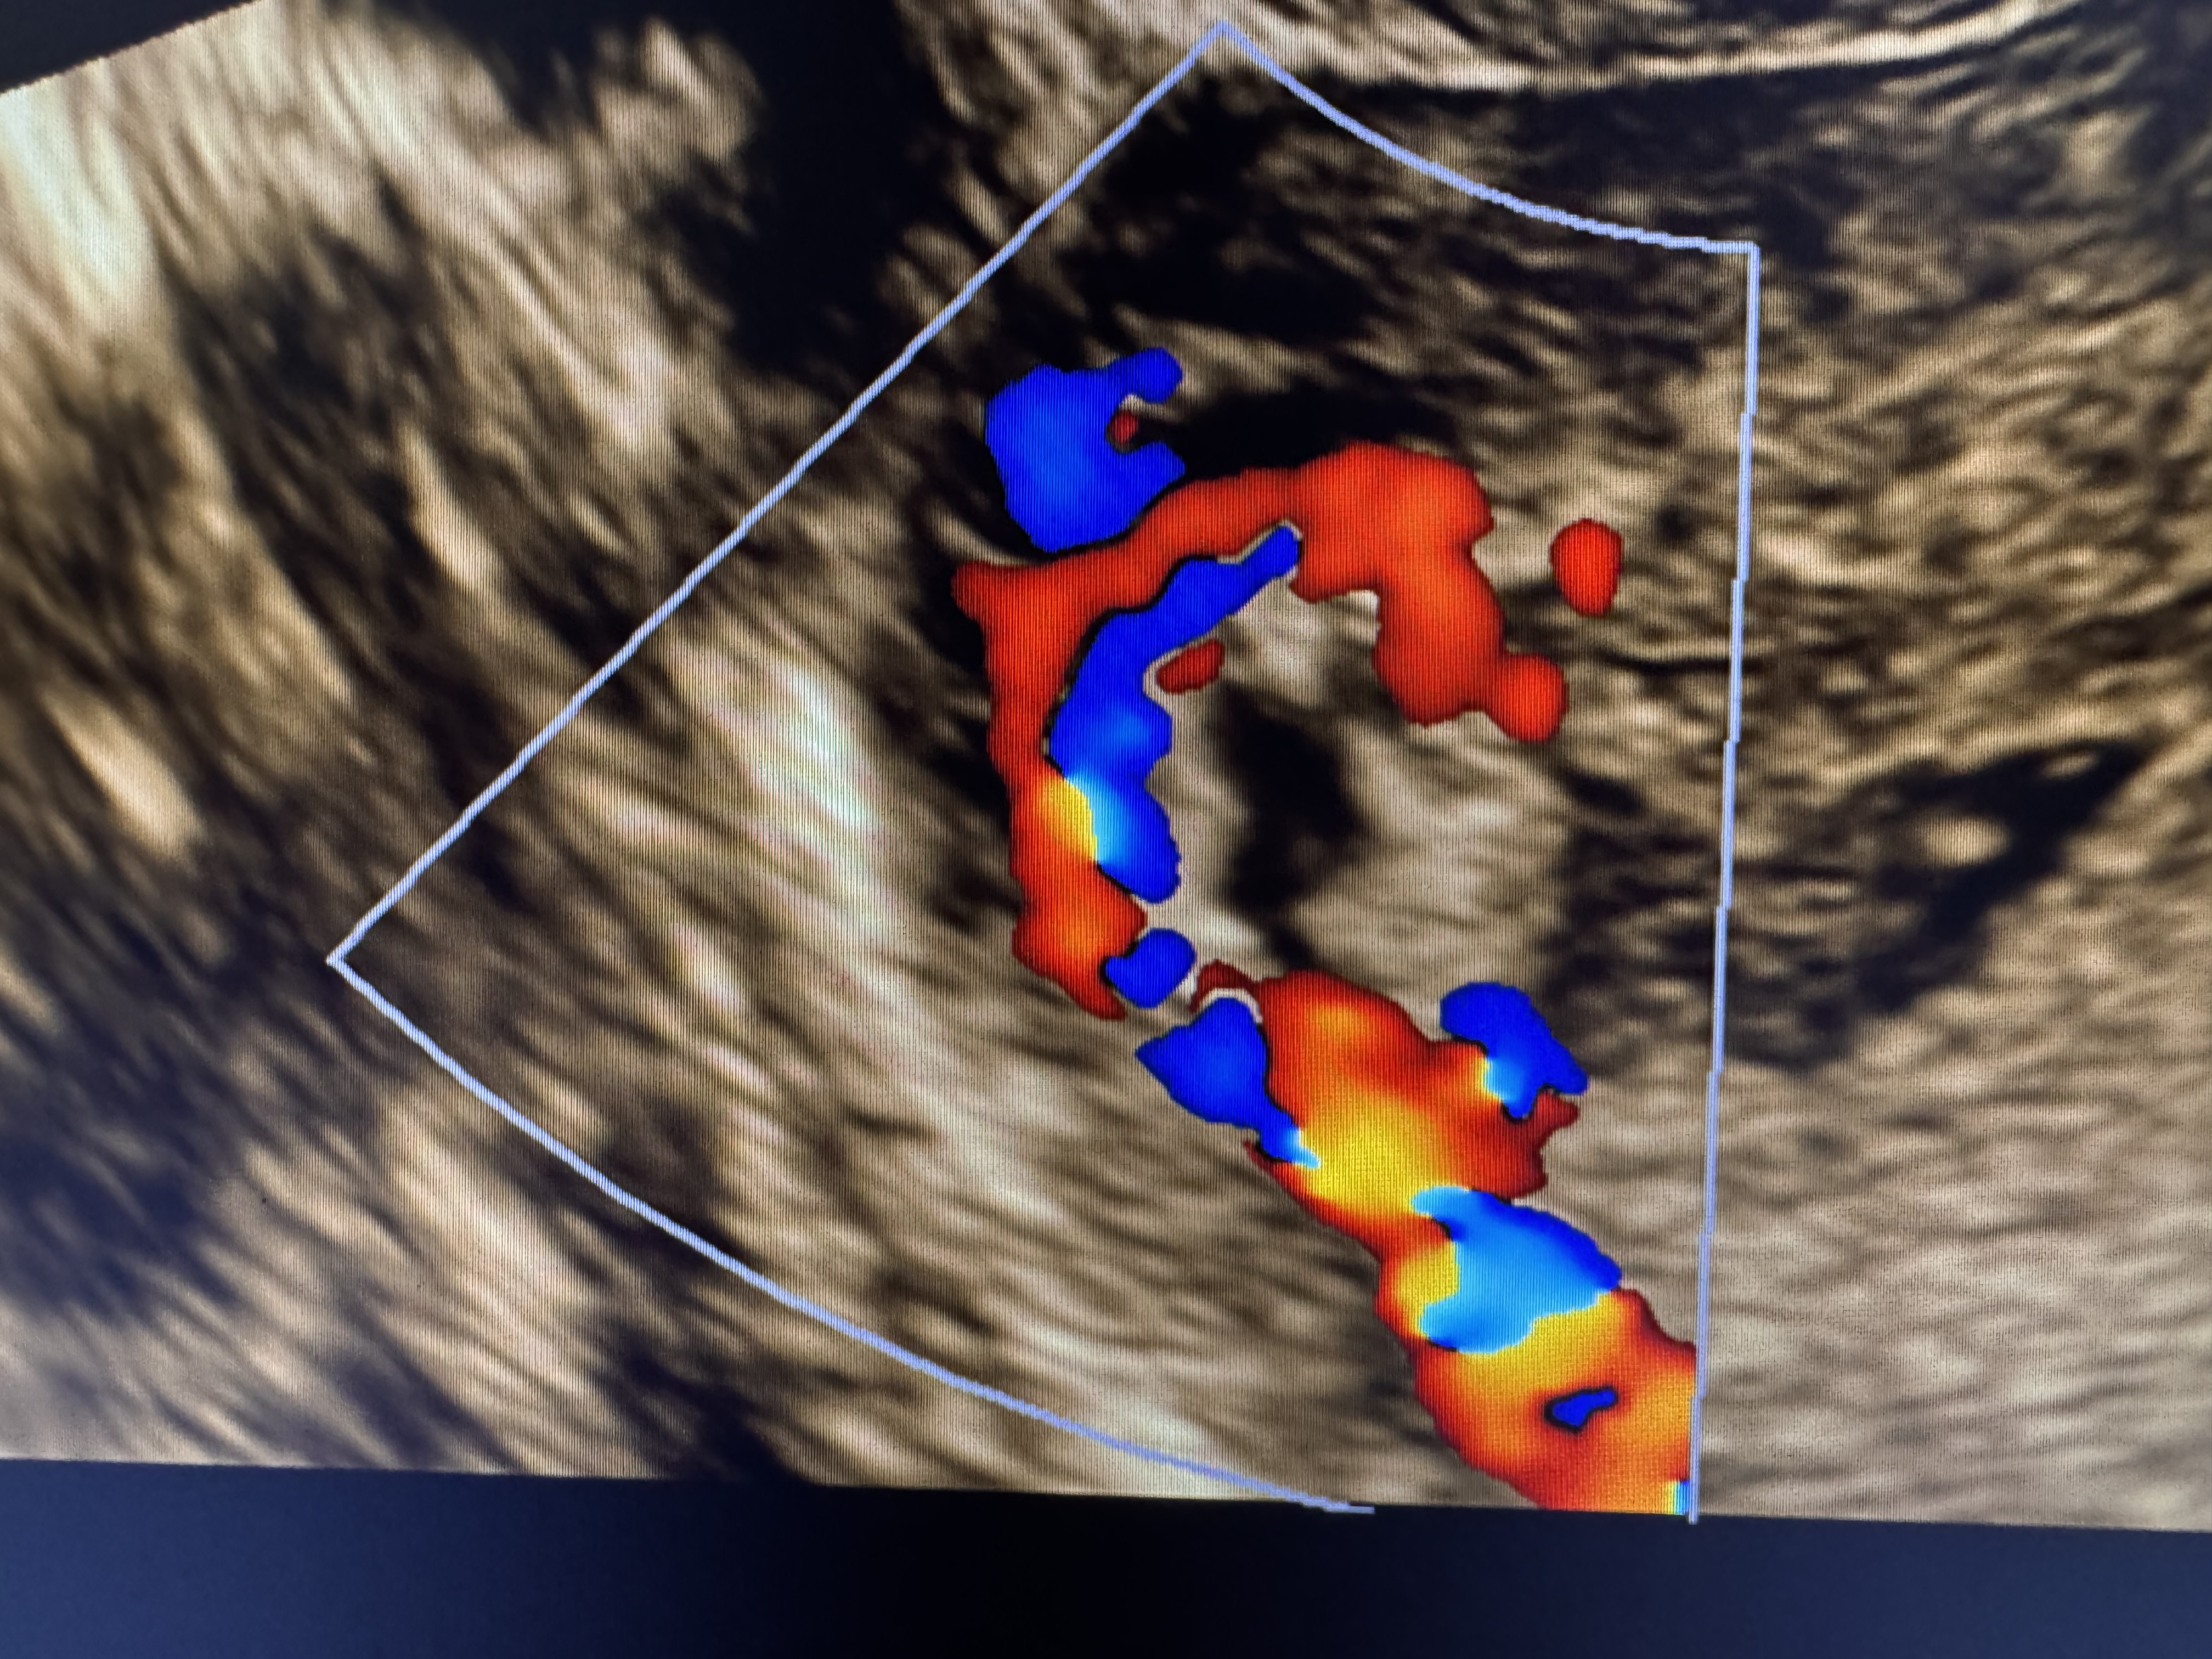

сделала 2.03 узи, нашли гематометру, остатки плодного яйца.

направили в стационар на чистку, сегодня сделали узи и подозревают новую беременность малого срока,а может и это от старой остатки, точно ответить мне не могут, хгч я сдавала от 27.02, 4254

Марина, добрый вечер, плодное яйцо вроде как и видят и хорион, врачи не могут ни подтвердить ни опровергнуть новую беременность,т.к если это она , то только все формируется, в любом случае, что-то со мной происходит, новая б на фоне старой, неполный пузырный занос или просто остатки старой беременности, конкретики нет, завтра назначена гистероскопия, пообщаюсь с врачом .. обновлю свой дневник, 99%, что будут делать выскабливание , а там ждать гистологию